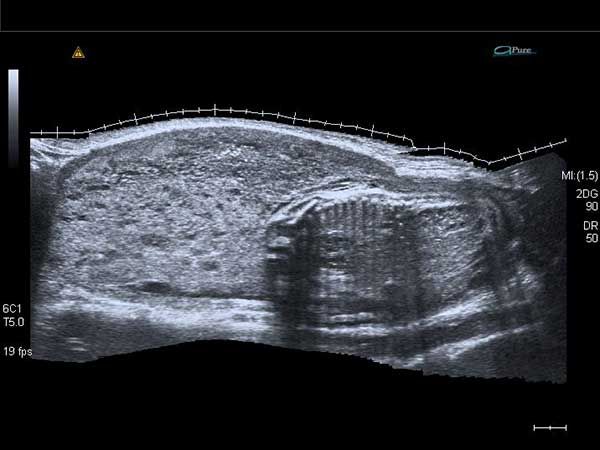

What is your diagnosis based on these images?